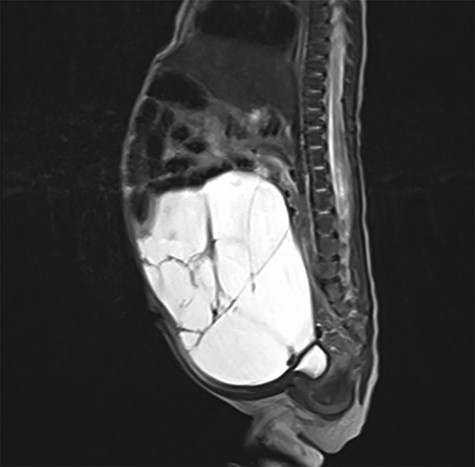

In the 18th week of gestation, routine ultrasound examination of a 35-year-old primigravida revealed a fetal cystic intra-abdominal mass occupying the entire abdominal cavity. A prenatal magnetic resonance imaging (MRI), performed in the 29th gestational week, showed a lymphatic cystic malformation measuring 12 × 7 × 9 cm (Fig. 1). In the 33rd gestational week, intestinal hypoperfusion due to compression by the malformation was suspected during an ultrasound examination. Therefore, a caesarean section was performed without complications.

Prenatal MRI in the 29th gestational week showing a multicystic septed mass occupying the complete abdominal cavity (white arrow).